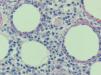

Fig. 3.—Llama la atención la disposición de los linfocitos atípicos que, junto con los restos nucleares, rodean a las adipocitos, formando un anillo alrededor de ellos. (Hematoxilina-eosina, ×200.)

En las pruebas complementarias destacaba una leucopenia de 2.700/l (neutrófilos 1.200/l, linfocitos 1.000/l), con serie roja y plaquetas normales, así como una lactato deshidrogenasa de 638 U/l. Se realizó una biopsia cutánea, en la que se observó una paniculitis predominantemente lobulillar a expensas de un infiltrado mixto linfohistiocitario, y no se detectaron microorganismos con las técnicas de Giemsa, ácido peryódico de Schiff y Ziehl-Neelsen. Los cultivos de la biopsia cutánea para bacterias, hongos y micobacterias fueron negativos. Se realizó una segunda biopsia de una nueva lesión nodular eritematosa en cara anterior, de pierna izquierda aparecida 15 días después. En esta se observaba un infiltrado en el tejido celular subcutáneo, predominantemente lobulillar, compuesto por una población polimorfa que incluía principalmente linfocitos con atipia nuclear, núcleos hipercromáticos y contorno irregular, junto con células macrofágicas que contenían restos nucleares en sus citoplasmas. Se observaban abundantes figuras de mitosis y prominente cariorrexis (fig. 2). Llamaba la atención la disposición de los linfocitos atípicos que, junto con los restos nucleares, rodeaban a las vacuo-las lipídicas, formando un anillo alrededor de ellas (fig. 3). Las células linfocitarias neoplásicas expresaban CD43, CD3, CD8 y eran negativas para CD20, CD79 alfa, CD4, CD56 y CD30. El índice proliferativo era de alrededor del 25 %. El estudio molecular mediante reacción en cadena de la polimerasa de los genes del receptor de las células T no fue valorable. Los estudios de extensión fueron normales y en la médula ósea no se encontraron infiltraciones ni hemofagocitosis.